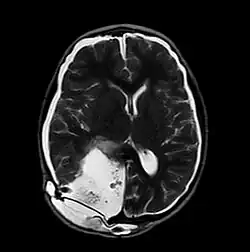

MRI of Pseudomeningocele in 8 years old male patient | |

A pseudomeningocele is an abnormal collection of cerebrospinal fluid (CSF) that communicates with the CSF space around the brain or spinal cord. In contrast to a meningocele, in which the fluid is surrounded and confined by dura mater, in a pseudomeningocele, the fluid has no surrounding membrane, but is contained in a cavity within the soft tissues.